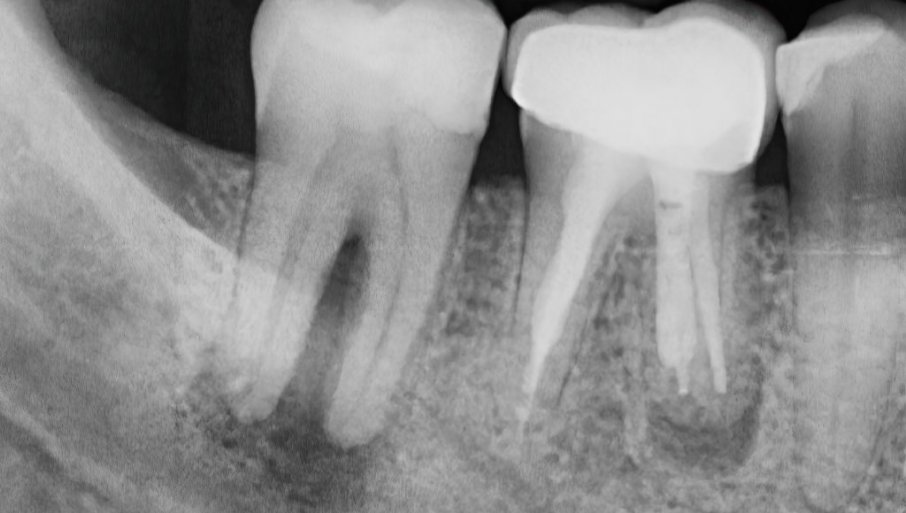

Али прво, тим је морао да утврди колико добро зубни имплантати преносе звук у поређењу са природним зубима и мастоидном кости иза уха, на које се друге врсте слушних апарата ослањају да раде.

Тако су истраживачи применили звучне тонове на имплантате, природне зубе и мастоидне кости 38 особа са оштец́ењем слуха и једним зубним имплантом.

За широк спектар фреквенција, волонтери су могли да чују звукове кроз имплантате, као и, или боље, него кроз природне зубе или мастоидне кости, извештава тим.

Чинило се да имплантати предњих зуба функционишу нешто боље од зубних имплантата према задњем делу вилице.

То може бити зато што је вилична кост на предњем делу уста тврђа од вилице позади, спекулише тим.

Доњи зуби и имплантати су радили као и горњи за преношење звука.